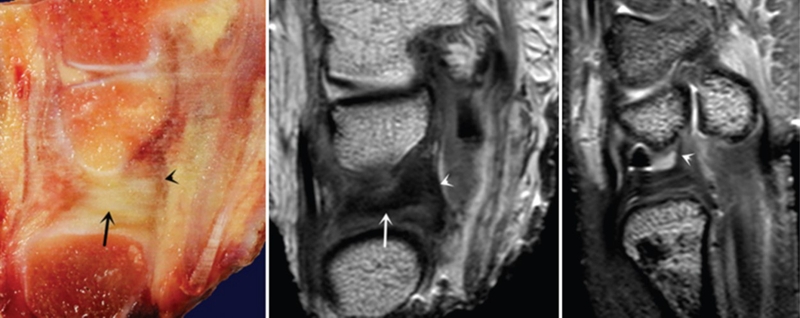

ⅠA,TFCC中心穿孔,A、B三角软骨盘正常弓形低信号缺损;C轴位显示三角软骨盘中心的高信号区与D关节镜一致

ⅠB,TFCC尺侧撕裂;TFC尺侧附着处信号增高

ⅠC,尺三角韧带撕裂

ⅠD,TFC桡侧撕裂,桡侧附着处及桡尺关节处信号增高

ⅡA,TFC局部变薄,但结构完整

ⅡB,TFC局部变薄,但结构完整,月骨软骨厚薄不均

ⅡC,TFC中心撕裂,月骨软化,月三角韧带完整

ⅡD,TFC中心撕裂,月骨软化,月三角韧带缺如

图30 ⅡE,TFC中心撕裂,月骨、尺骨软骨软化,月三角韧带缺如,桡尺关节骨质增生